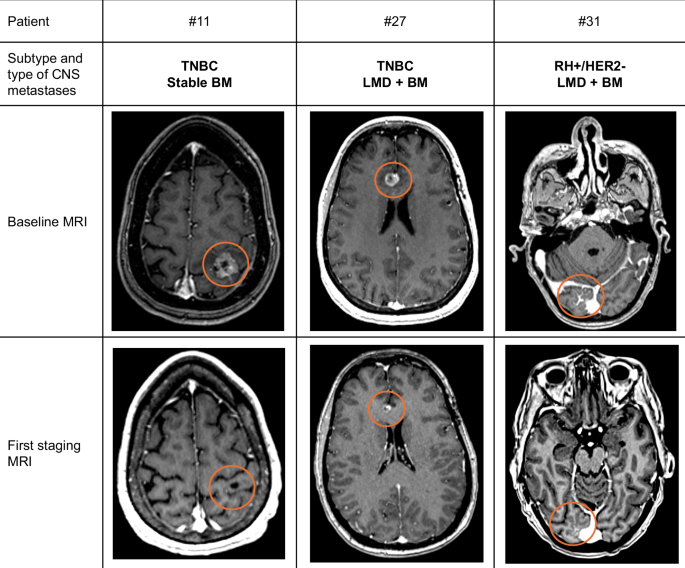

Baseline and Central Nervous system (CNS) response assessment by MRI Brain imaging of patients with metastatic breast cancer patients with CNS metastases treated with sacituzumab govitecan. LMD: leptomeningeal disease;BM: Brain Metastases. Patient #11 with stable BM received RT (SRS) less than two months before the initiation of OS. Patient #27 was irradiated for 9 months on another lesion (temporal) and patient #31 did not receive any irradiation before the SG.

In our cohort of 33 patients with MBC with CNS metastases, SG demonstrated modest CNS and extra-CNS activity with a CNS-ORR, median CNS-PFS, and OS of 4/30 (13.3%), 2.9 months (95%CI: 2.0–4.3), and 6.9 months (95%CI: 3.1–10.2), respectively. However, we did not observe any centrally-confirmed CNS responses in the seven patients with active BM. Furthermore, both patients with stable BM and CNS response after SG also received RT less than two months before the start of SG. Responding lesions were irradiated.